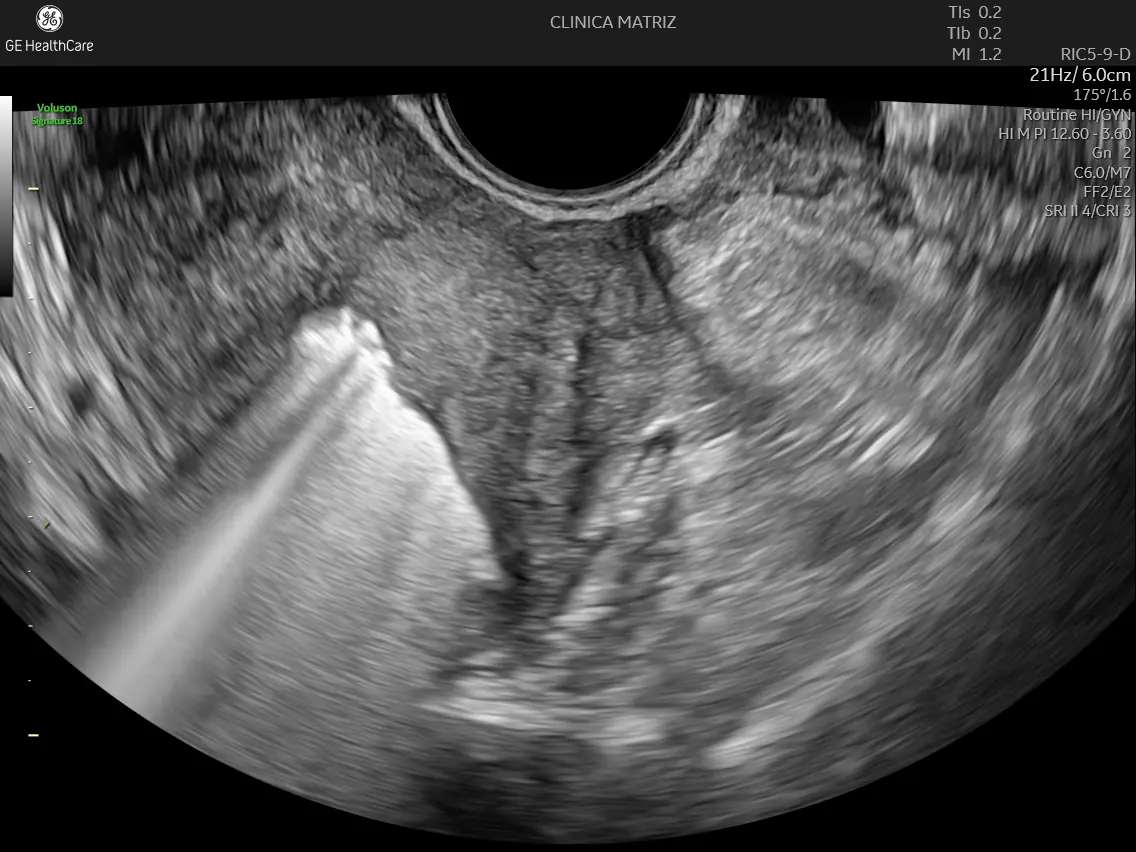

A histerossonossalpingografia é um exame de ecografia ginecológica que permite avaliar a cavidade uterina e a permeabilidade das trompas de Falópio sem recorrer a radiação. Ao contrário de outros métodos, este não exige anestesia e é realizado em ambiente de consulta por um médico ginecologista especializado.

Este é um exame realizado através de ecografia transvaginal. Introduzimos um cateter muito fino e flexível pelo colo do útero para instilar uma solução de contraste específica (espuma). É o movimento deste líquido que nos permite desenhar a anatomia interna e detetar qualquer obstrução.

O processo demora cerca de 20 a 30 minutos. O nível de desconforto é habitualmente ligeiro e comparável a uma cólica menstrual. Como a recuperação é imediata, podes retomar o teu dia logo após saíres da clínica.